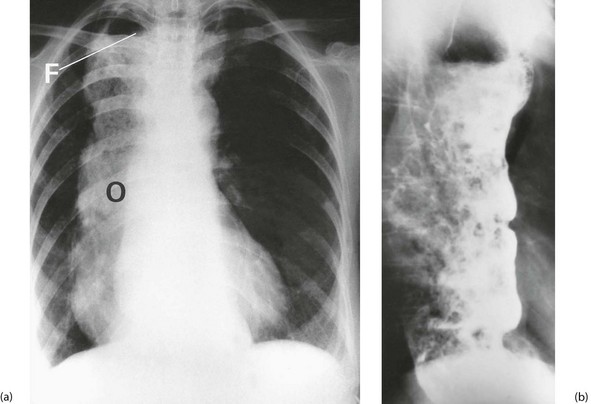

Clinically, the cardiac sphincter becomes constricted and the proximal oesophagus dilates with accumulated fluid and solids. Difficulty in swallowing is the usual presenting symptom, together with halitosis, weight loss, reflux of food into the back of the throat. Solids tend to sink to the lower end of the dilated oesophagus, whereas fluids spill over into the trachea causing spluttering dysphagia (see Ch. 18, p. 249) and coughing, particularly at night. Vomiting and retrosternal pain may occur in more severe cases.

Chest X-ray may show the mediastinal shadow is widened by a dilated oesophagus; sometimes a fluid level in the oesophagus is visible behind the heart Fig. 22.7(b). At endoscopy the typical appearance is of a capacious distal oesophagus, usually with food and fluid residue, and a tight lower oesophageal sphincter that may or may not admit the tip of the gastroscope. It is important to see the oesophago-gastric junction to exclude an occult neoplasm masquerading as achalasia (pseudoachalasia). Barium swallow examination reveals gross dilatation of the oesophagus with a tapering constriction (often described as a ‘bird’s beak’ or ‘rat’s tail’) at the lower end. The constriction barely allows contrast to enter the stomach (see Fig. 22.8). Under fluoroscopic screening, uncoordinated purposeless peristaltic waves can often be seen; these are described as tertiary contractions, distinct from normal coordinated primary and secondary contractions. Oesophageal manometry is the cardinal test for achalasia, demonstrating excessive lower oesophageal sphincter pressure that fails to relax on swallowing, and abnormal peristalsis in patients with a more chronic history.

As resistance to flow and pressure rises in the portal venous system, abnormal communications develop between the peripheral portal system and the systemic venous circulation. This is known as portal-systemic shunting. Multiple large veins appear in the peritoneal cavity and retroperitoneal area, making any form of abdominal surgery hazardous. Large submucosal veins also appear at the lower end of the oesophagus and gastric fundus, and are known as gastro-oesophageal varices (see Fig. 22.11). These varices can cause massive gastrointestinal haemorrhage, possibly related to rises in intravariceal pressure. Up to 40% of cirrhotic patients suffer variceal haemorrhage at some stage.